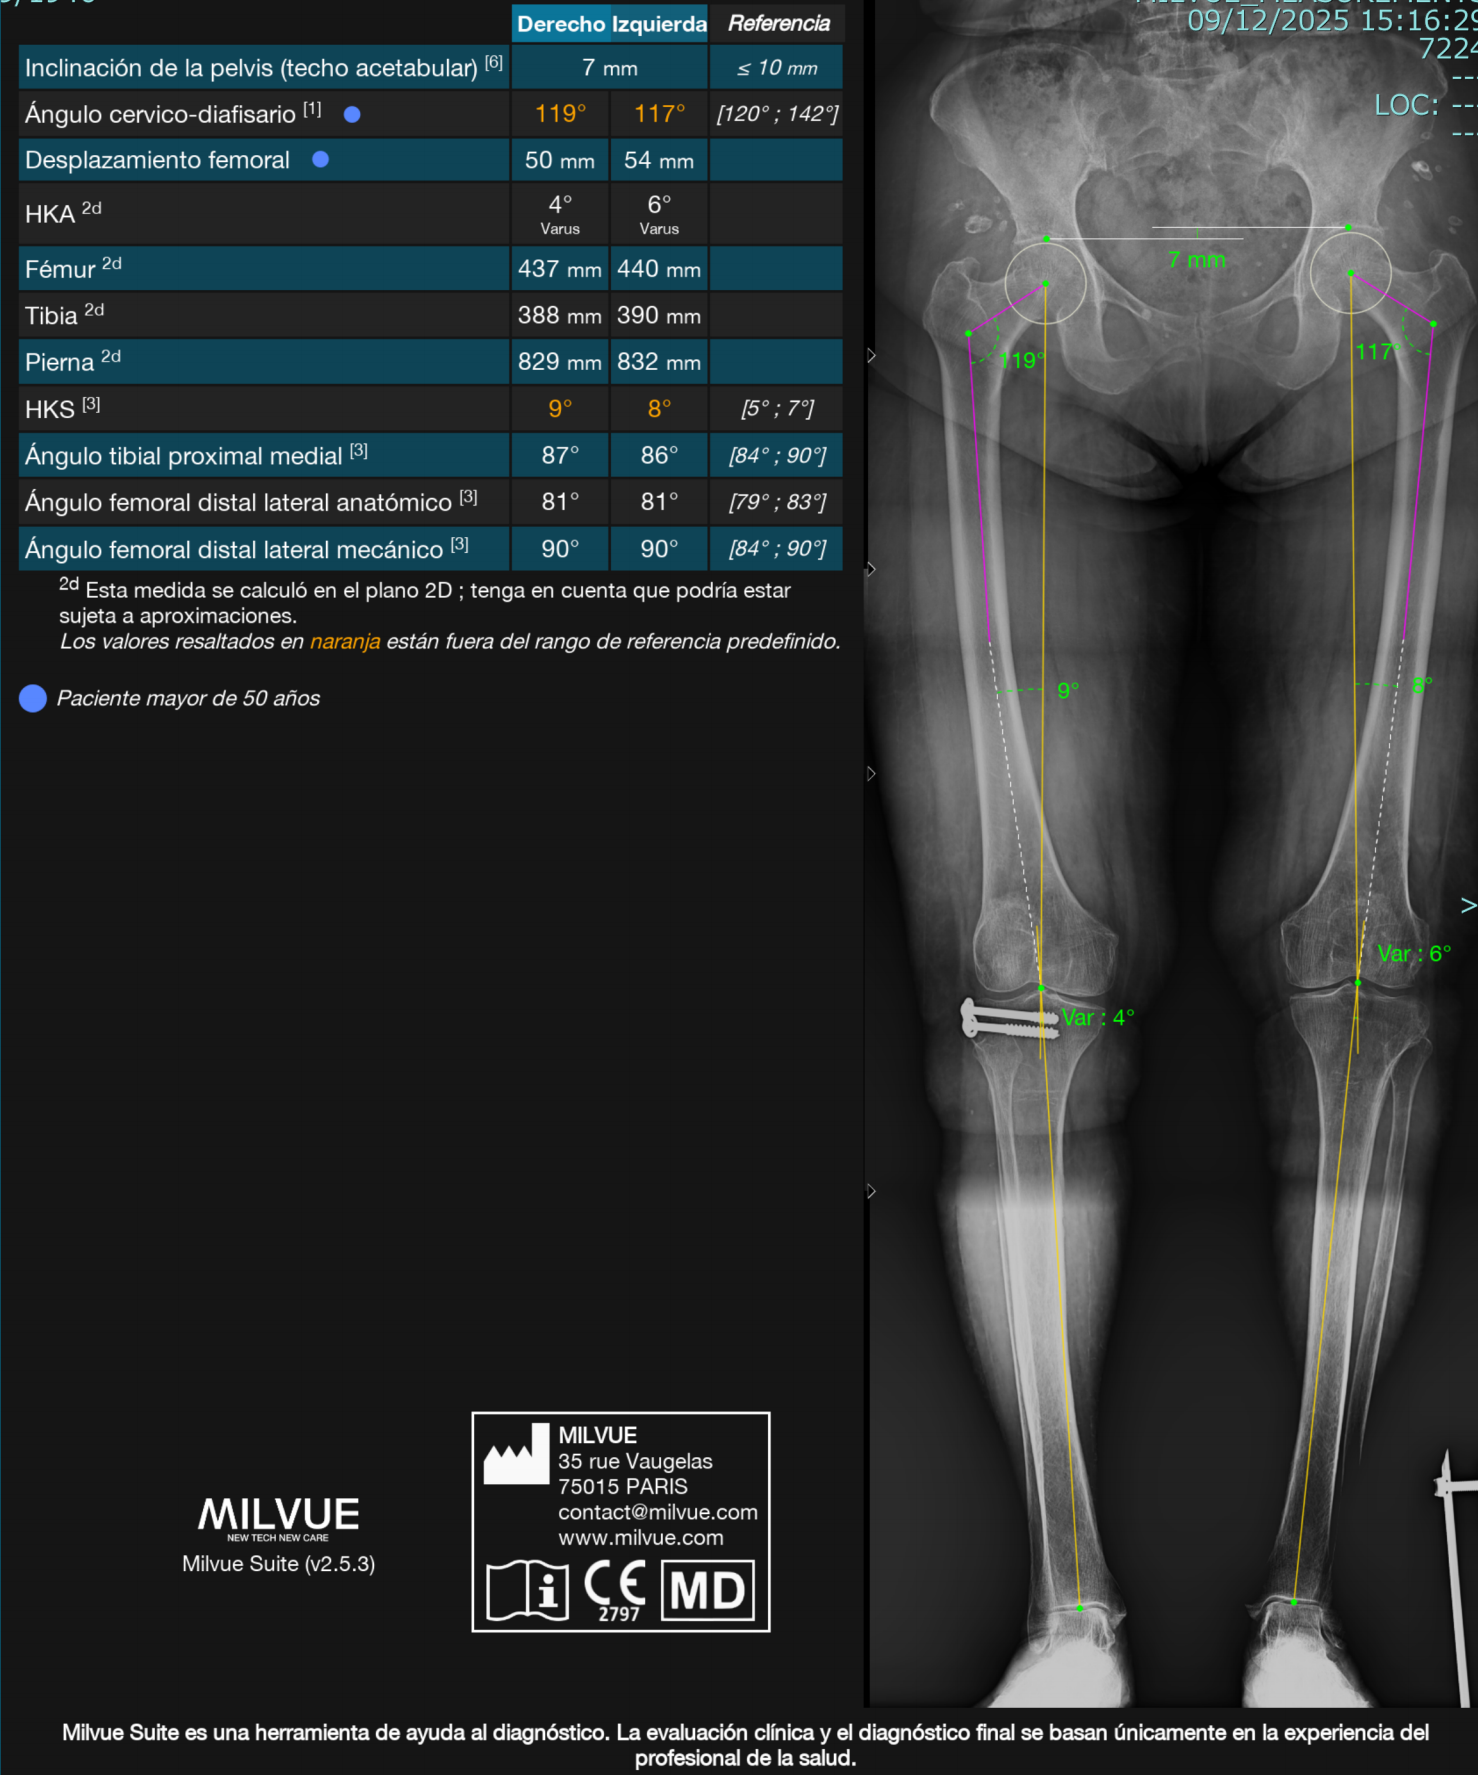

IA para Rayos X – Milvue

Milvue es una solución líder en inteligencia artificial aplicada a Rayos X, especialmente en el área musculoesquelética, con impacto clínico demostrado en servicios de urgencias.

#1 en detección automática de fracturas.

Detección de múltiples patologías en una sola imagen.

Reducción del tiempo de espera hasta en 1 hora.

Incremento del 20–30% en eficiencia diagnóstica.